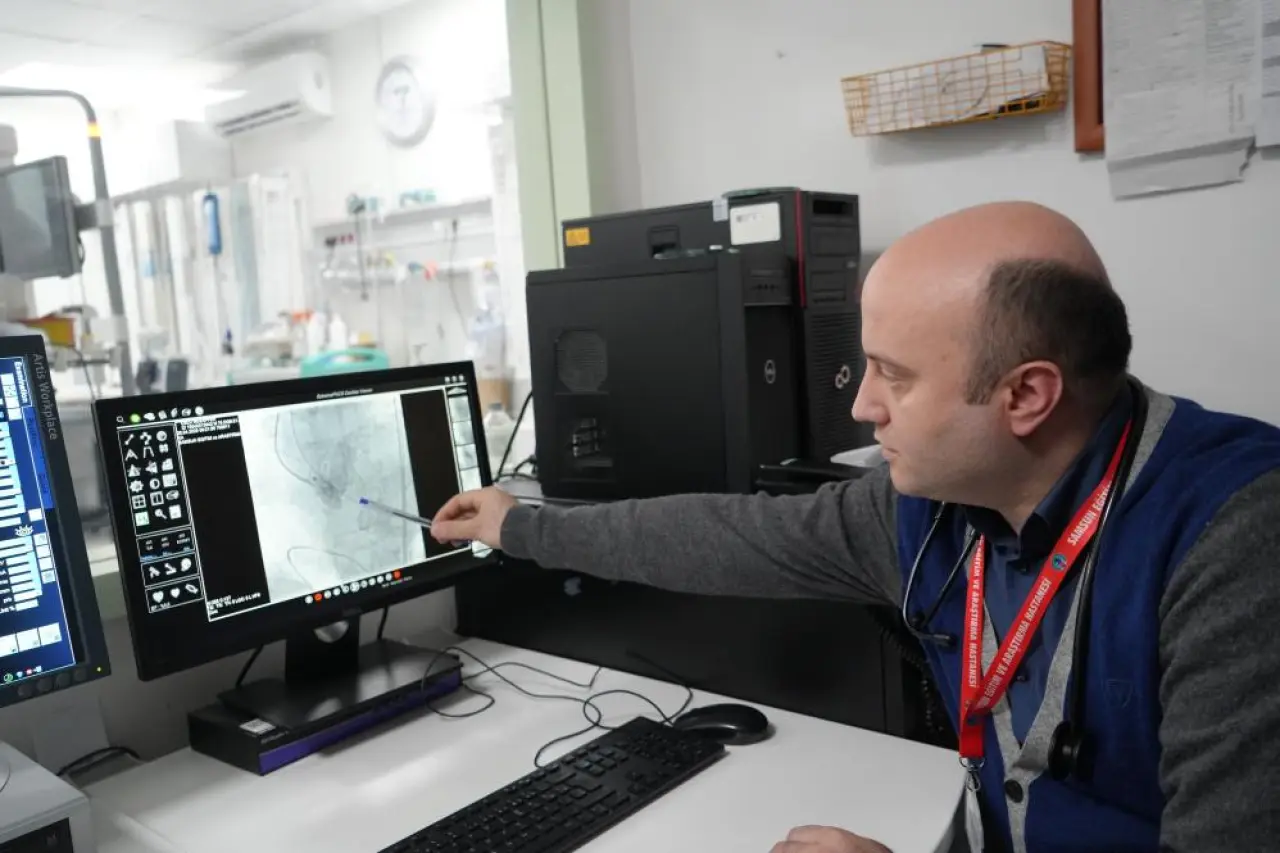

Operasyonu gerçekleştiren Samsun Üniversitesi Tıp Fakültesi Kardiyoloji Ana Bilim Dalı Öğretim Üyesi Doç. Dr. Mustafa Yenerçağ, “Hastamızda yaptığımız değerlendirmelerde, toplumda 100 bin kişide yalnızca 4 kişide görülen ‘quadricuspid’ yani dört yaprakçıklı aort kapağı tespit ettik. Literatür taramalarımızda bu tür kapağa TAVİ işlemi yapılan sadece 17 vaka bulabildik. Türkiye’den ise böyle bir vaka kaydına rastlayamadık,” dedi.

Yenerçağ, hastanın yaşı ve açık kalp ameliyatının taşıdığı yüksek risk nedeniyle TAVİ yöntemini tercih ettiklerini belirterek, “Açık ameliyat yerine kateter yardımıyla yapılan kapalı yöntemle başarı sağladık,” dedi.

Yaklaşık 50 dakika süren operasyonu gerçekleştiren ekipte Doç. Dr. Serkan Sivri, asistan doktorlar Berkan Öztürk ve Enes Kaya ile Anestezi Uzmanı Aynur Kaynar yer aldı. İşlem sonrası hasta bir gün yoğun bakımda, ardından serviste izlem altına alındı.